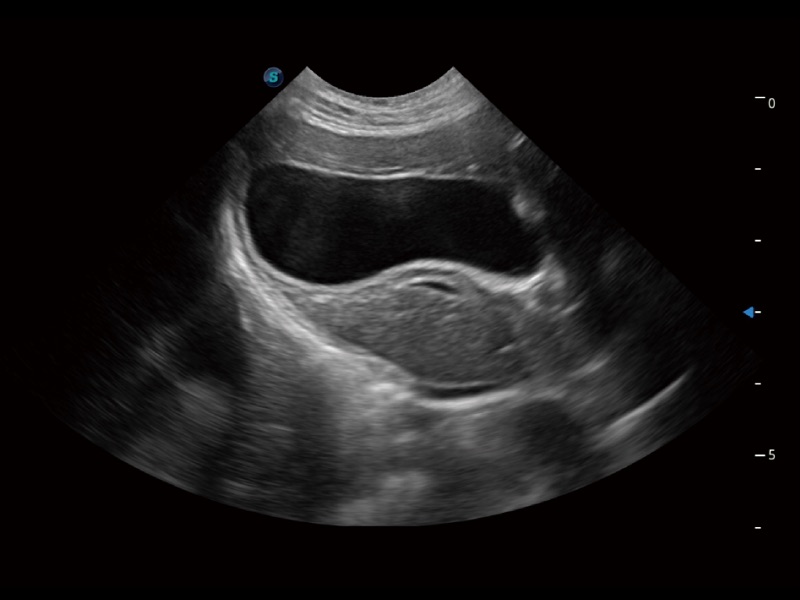

一键自动识别膀胱壁及自动测量膀胱容积,不受膀胱形状和大小的限制,帮助医生快速精准获得测量的数据。

ProPet 70专为动物医生设计,对不同的动物体型和生理结构作出了针对性的优化。通过动物影像专用软件,可满足个性化的应用需求,帮助动物医生获得更精确的诊断数据。

为精细结构及组织边缘提供高清晰度的图像和更大的成像视野。帮助减轻医生的用眼疲劳,快速精准获得测量的数据。